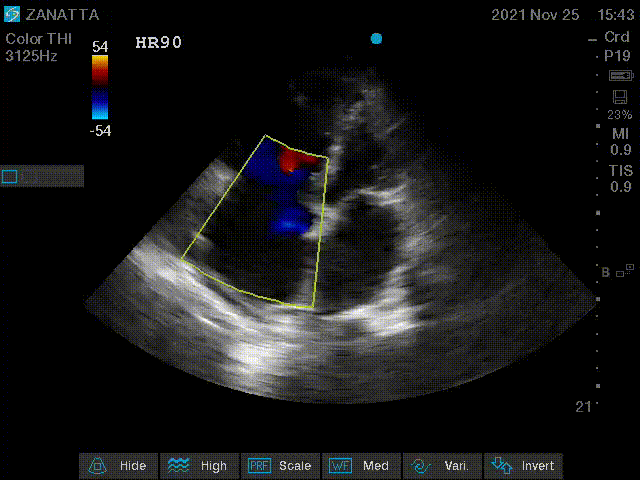

Onto colour doppler imaging.

Apical Four Chamber with Colour